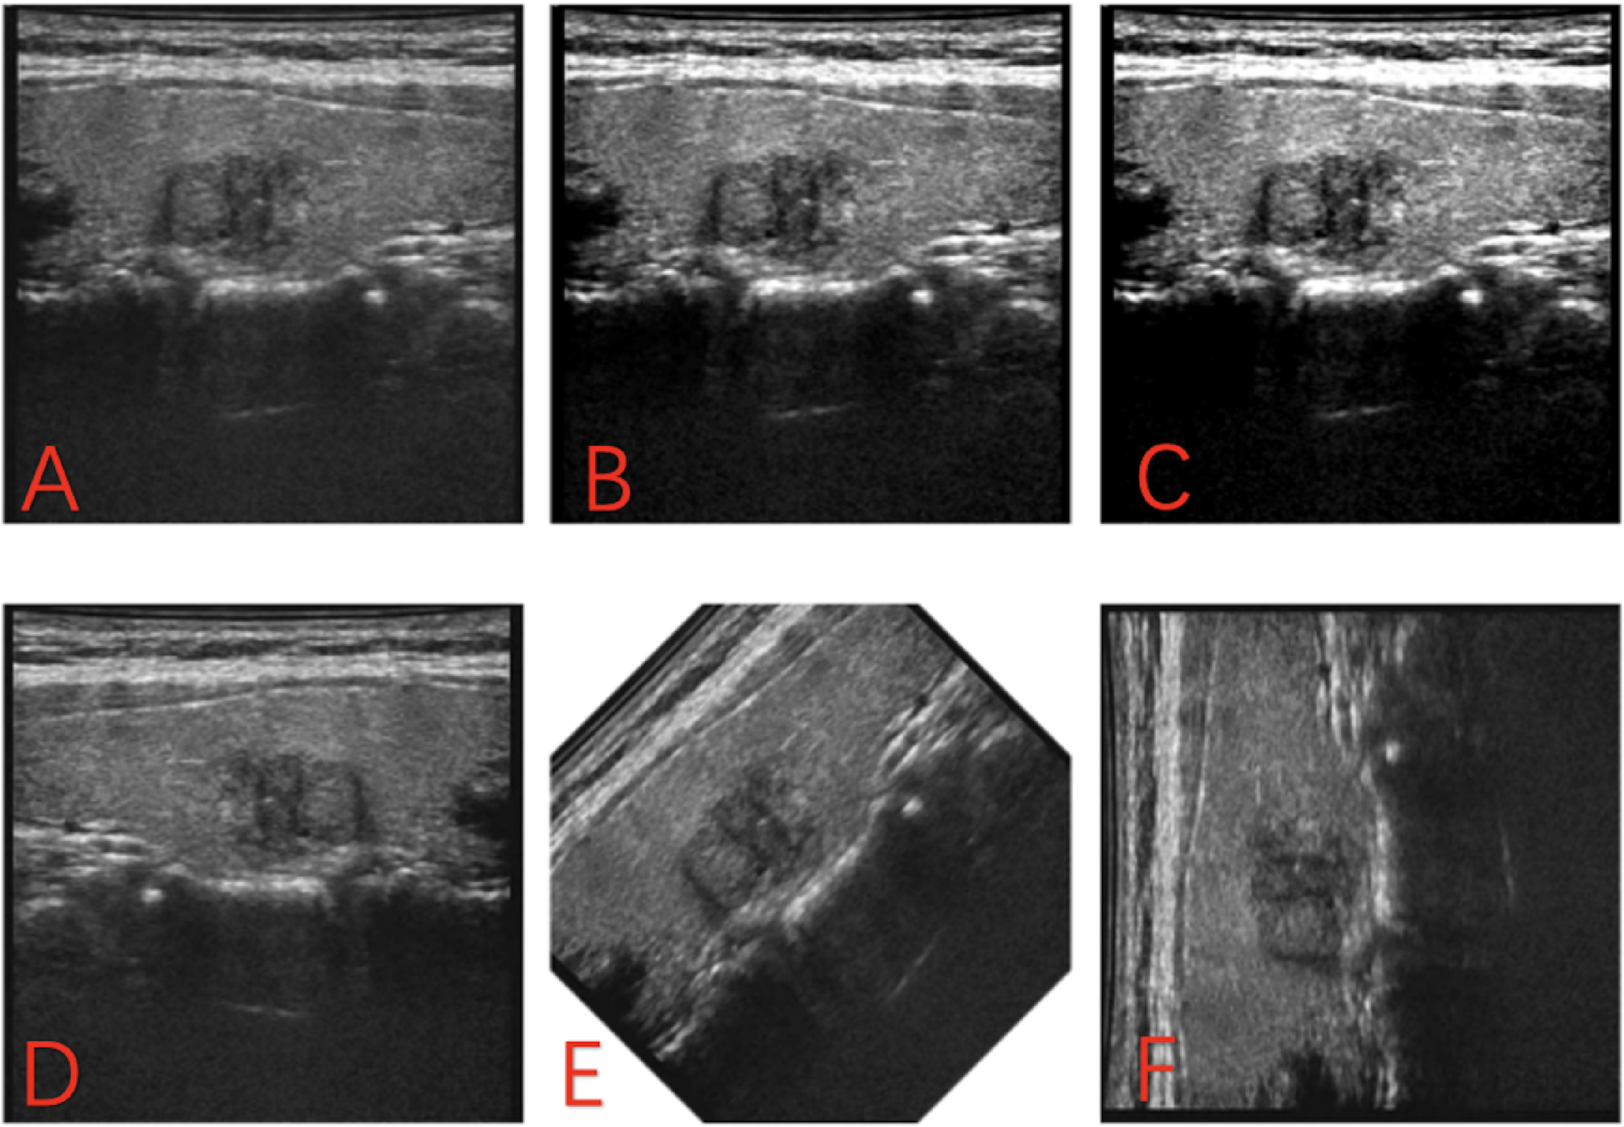

Fig. 1

(A): The original images were converted to grayscale. (B) Amplification through contrast enhancement (1.5x). (C) Amplification through contrast enhancement (2.0x). (D) Amplification through inversion. (E) Amplification through inversion rotations (45°). (F) Amplification through inversion rotations (90°).